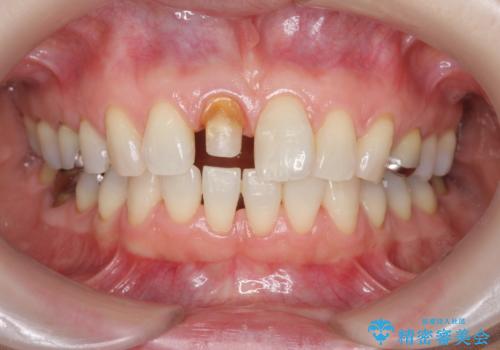

前歯の変色 セラミック審美補綴

- 前歯の変色の改善を希望され来院されました.

以前に神経が死に、根管治療を行った歯の変色が認められたためセラミックによる審美補綴治療を計画します。

神経治療を行い補綴(かぶせもの)治療を行わないと、変色が目立ち審美障害を起こすことがあります。